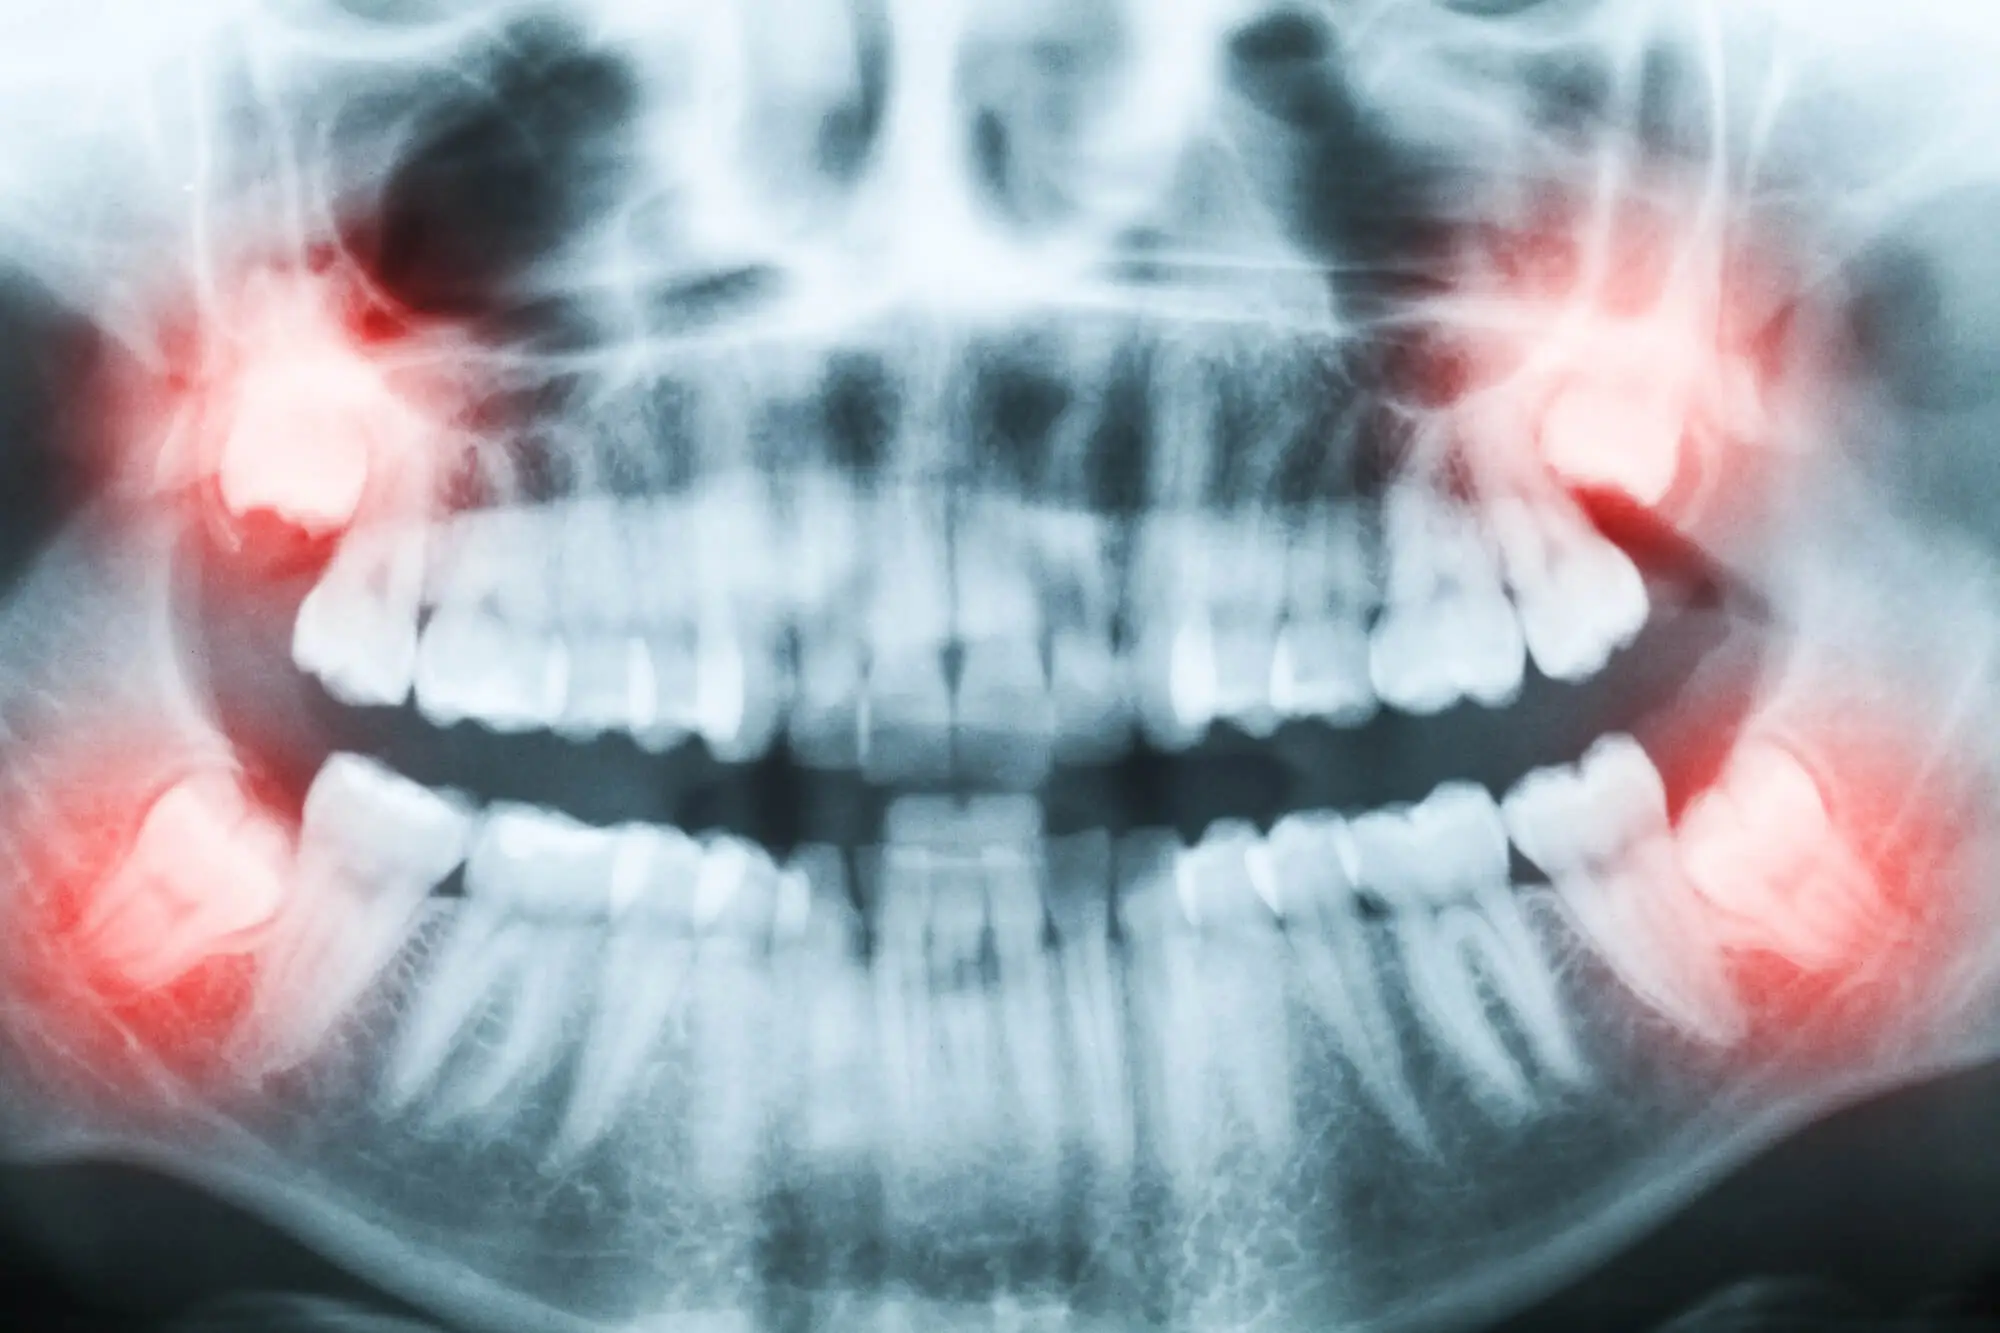

When this happens, the lack of space can cause them to grow at odd angles or become trapped (impacted) under the gum and jawbone. Not everyone develops wisdom teeth, and they’re not always impacted. But when they do come, they typically appear between 17 and 25.

There are 4 types of impacted wisdom teeth depending on their position and angle in the jaw:

- Mesial Impaction: The tooth is tilted forward toward the front of the mouth (most common).

- Distal Impaction: The tooth is angled toward the back of the mouth (less common).

- Vertical Impaction: The tooth is upright but doesn't fully erupt due to a lack of space.

- Horizontal Impaction: The tooth lies completely on its side, pushing into the neighboring molar (most severe).